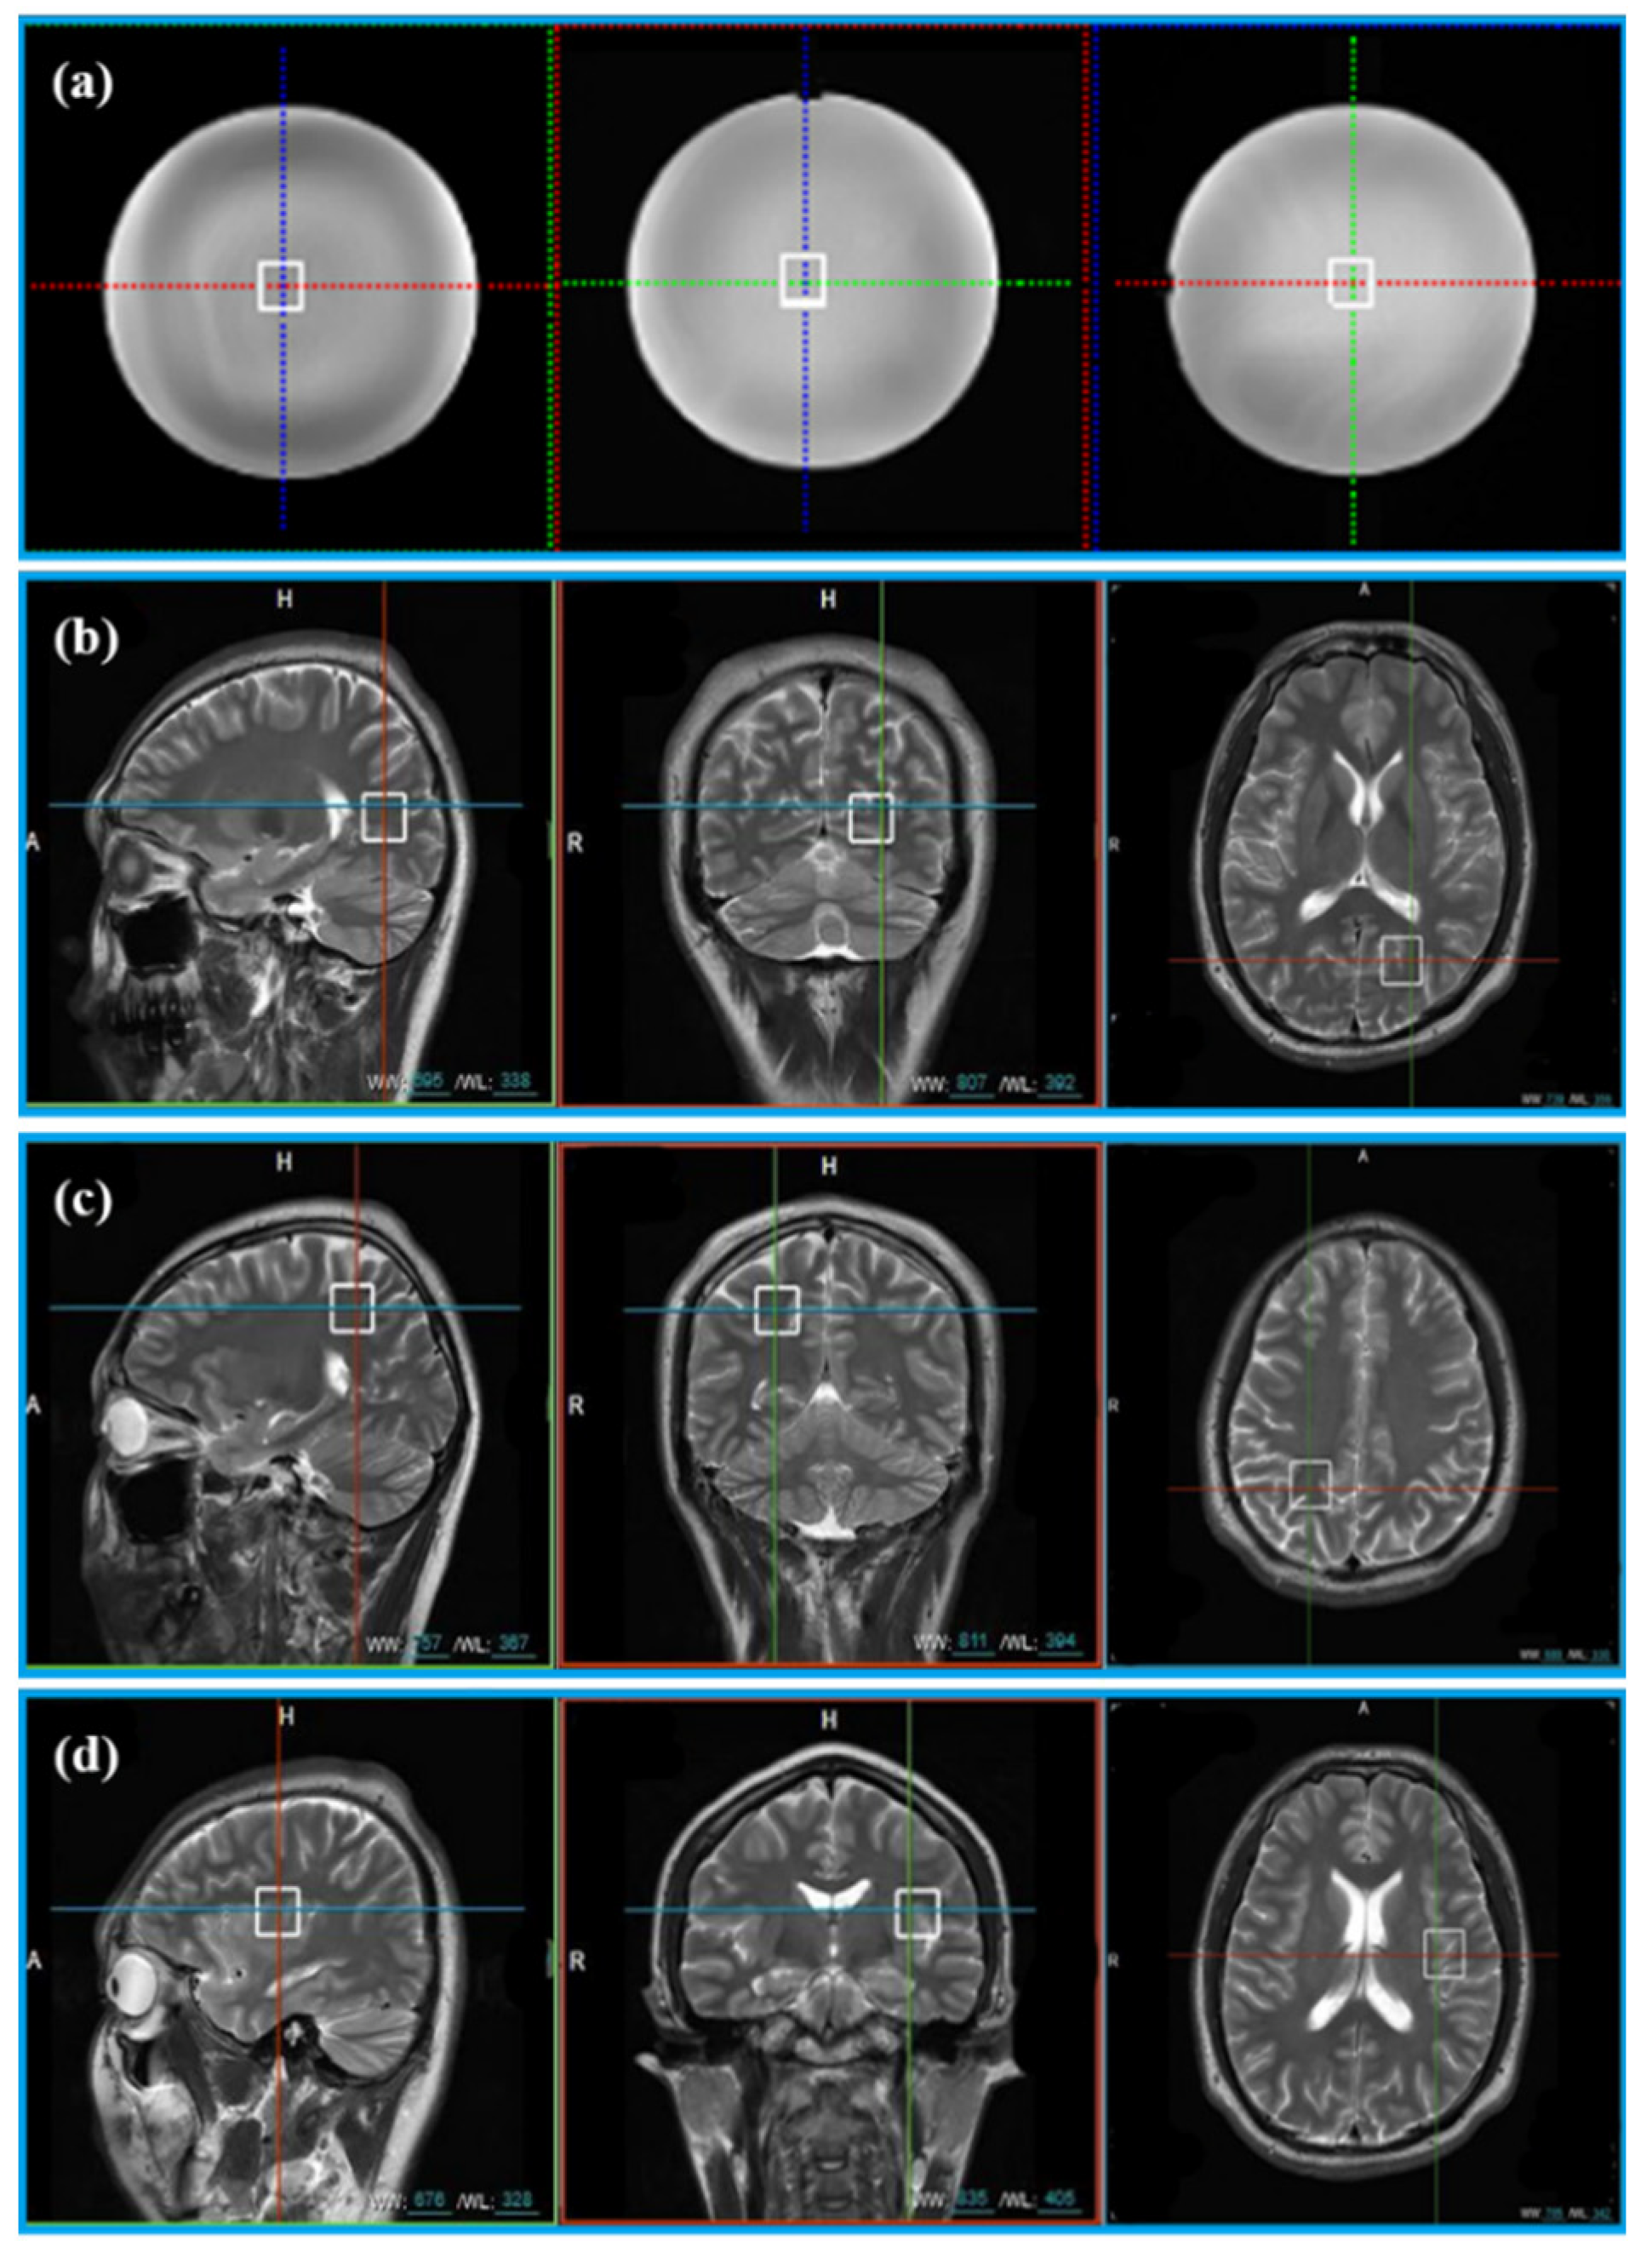

The General Electric golden standard phantom sphere was used for phantom experiments. Voxel locations of the sphere are shown in Figure 2a. The simulated correlation noise between coils was added to phantom experiments with different noise levels [13,16,17]. The simulated noise of each repeated sampling was independently generated according to the in vivo spectrum as follows.

Figure 2.

The location of voxels acquired from phantom and 11 healthy volunteers. (a) Voxel location of the phantom; (b) voxel LA, (c) voxel LB, and (d) voxel LC are the voxel locations of 11 healthy subjects.

In vivo data were acquired from 11 healthy volunteers with the approval of the Institutional Review Board of Shanghai Jiao Tong University. Informed consent was obtained from all volunteers before the study began. Three healthy volunteers were scanned at three different voxel locations (Location A (LA), Location B (LB), and Location C (LC)) in Figure 2b–d. Five healthy subjects were scanned at the LA only and other three healthy subjects were scanned at LB and LC. Finally, totally, 20 MRS were acquired for validation (see Table 1 for details).